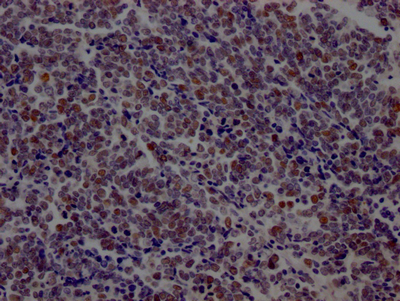

IHC image of CSB-RA877322A0HU diluted at 1:100 and staining in paraffin-embedded human placenta tissue performed on a Leica BondTM system. After dewaxing and hydration, antigen retrieval was mediated by high pressure in a citrate buffer (pH 6.0). Section was blocked with 10% normal goat serum 30min at RT. Then primary antibody (1% BSA) was incubated at 4℃ overnight. The primary is detected by a Goat anti-rabbit IgG polymer labeled by HRP and visualized using 0.05% DAB.